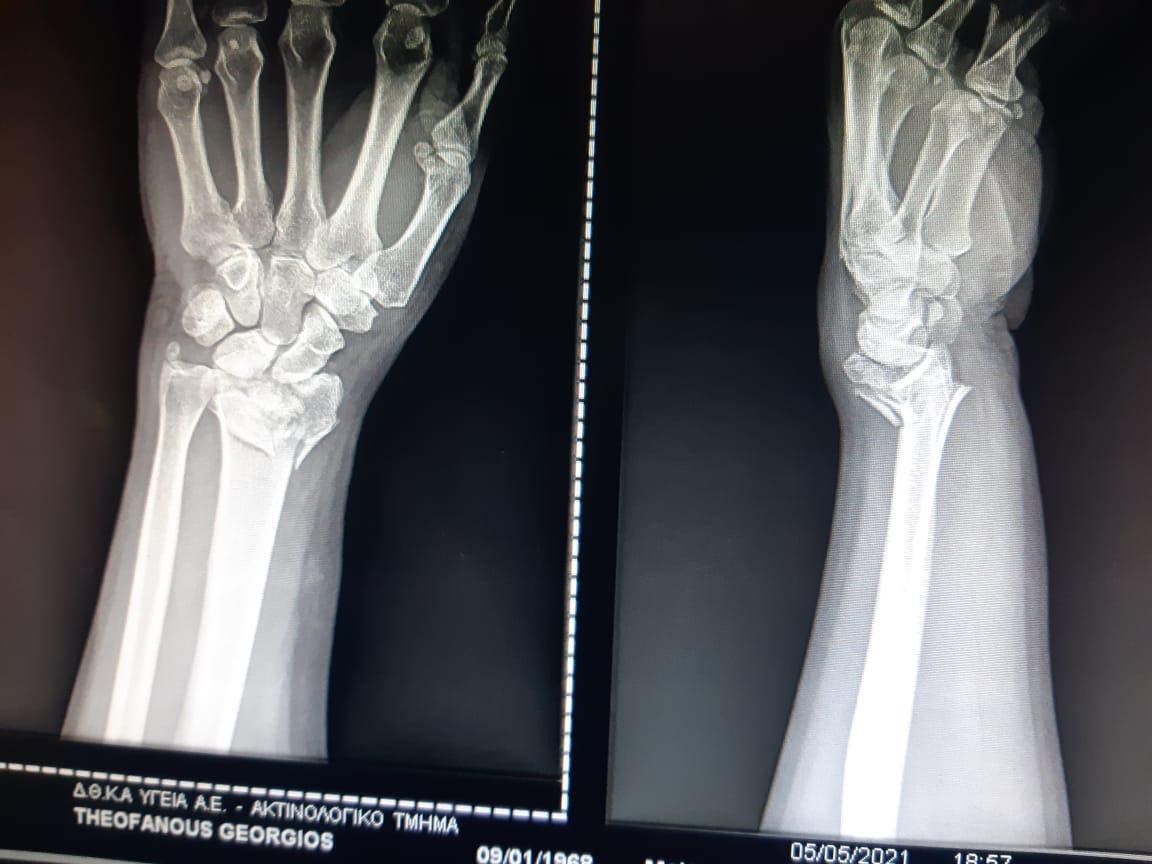

Ο συνθέτης μάλλον έπεσε, αλλά δεν έχουν γίνει γνωστές περισσότερες λεπτομέρειες για το ατύχημα. Όπως είπε ο Γιώργος Λιάγκας, ο τραυματισμός είναι σοβαρός καθώς υπέστη κάταγμα και η αποθεραπεία θα διαρκέσει τουλάχιστον δύο μήνες.